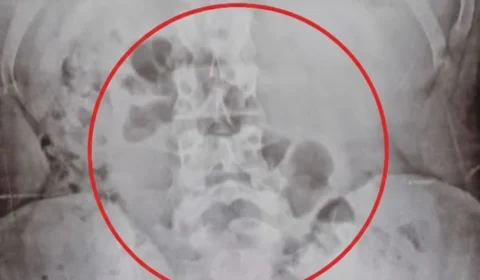

Mãe é flagrada com drogas no estômago ao transportar substâncias para o filho em Porto Velho

Suspeita foi detida após intervenção policial; entorpecentes estavam escondidos internamente.